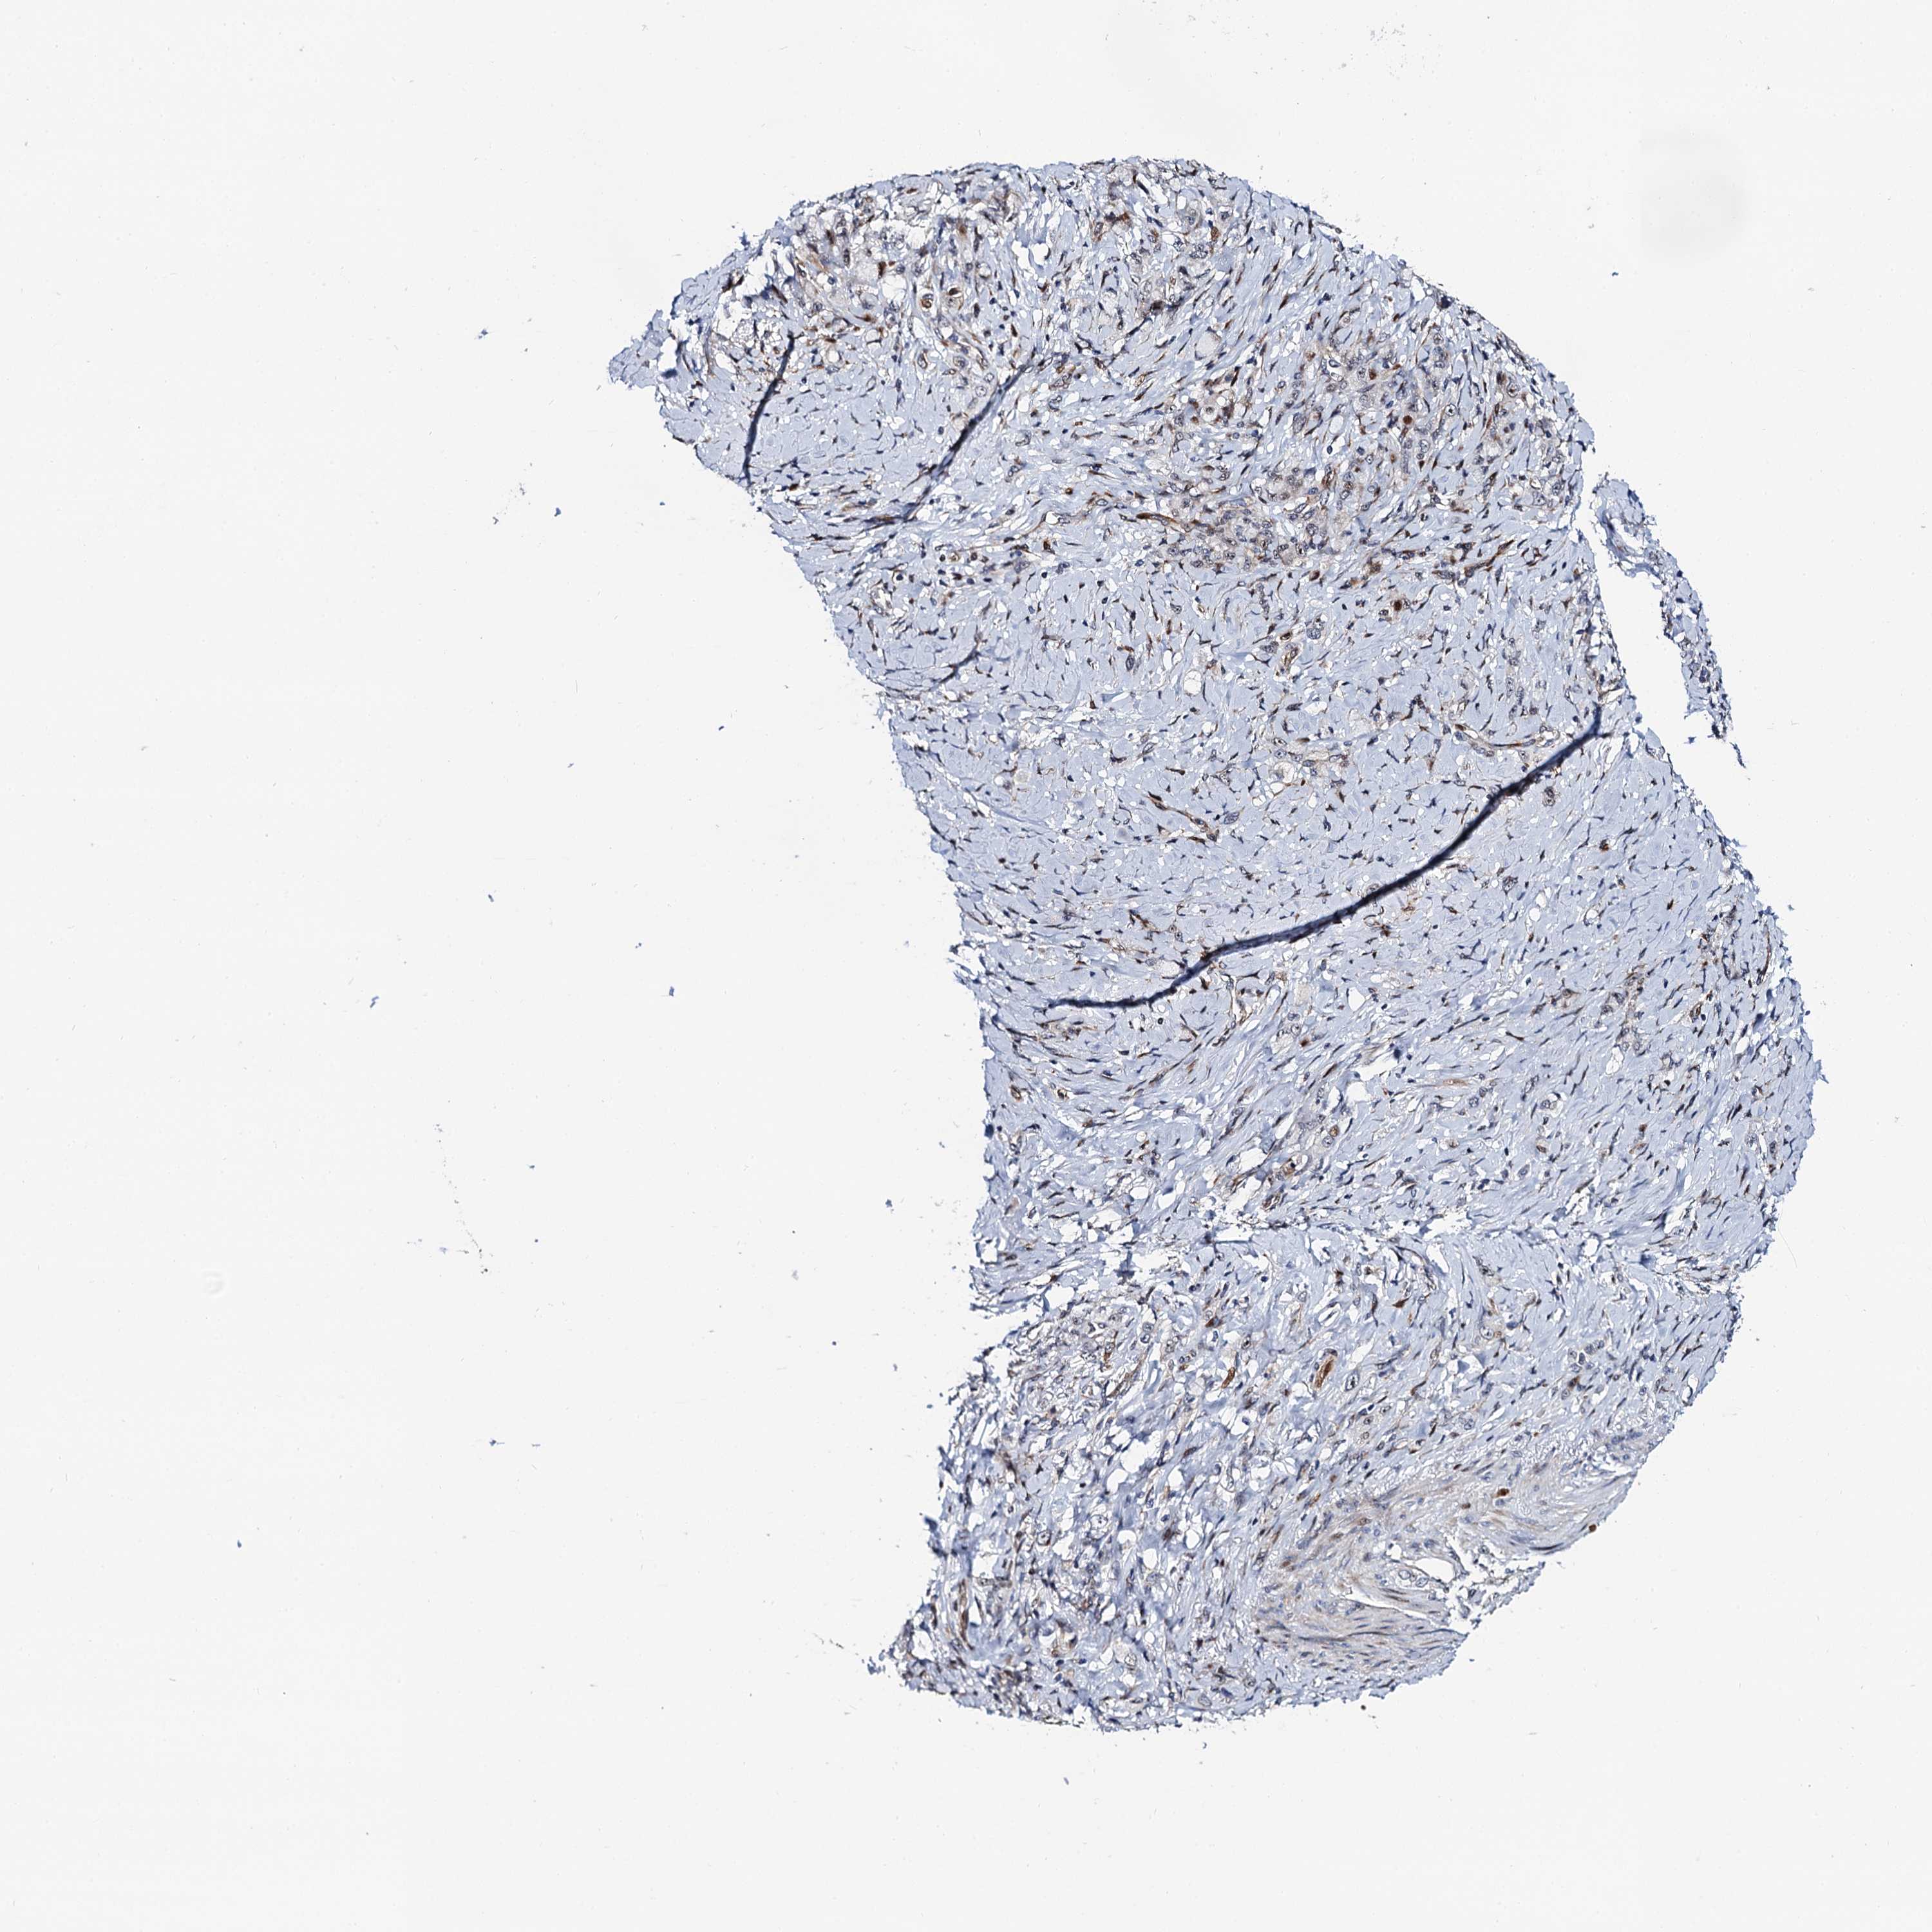

STOMACH CANCER - Protein expressioni

A mouse-over function shows sample information and annotation data. Click on an image to view it in a full screen mode. Samples can be filtered based on level of antibody staining by selecting one or several of the following categories: high, medium, low and not detected. The assay and annotation is described here.

Note that samples used for immunohistochemistry by the Human Protein Atlas do not correspond to samples in the TCGA dataset.

Antibody stainingi

Antibody staining in the annotated cell types in the current human tissue is reported as not detected, low, medium, or high, based on conventional immunohistochemistry profiling in selected tissues. This score is based on the combination of the staining intensity and fraction of stained cells.

Each image is clickable and will lead to virtual microscopy that enables deeper exploration of all samples and also displays staining intensity scores, fraction scores and subcellular localization as well as patient and tissue information for each sample.

Antibody HPA039901

Antibody HPA040006

Staining

High

Medium

Low

Not detected

Intensity

Strong

Moderate

Weak

Negative

Quantity

>75%

75%-25%

<25%

None

Location

Nuclear

Cytoplasmic/membranous

Cytoplasmic/membranous,nuclear

Adenocarcinoma, NOS

Adenocarcinoma, High grade